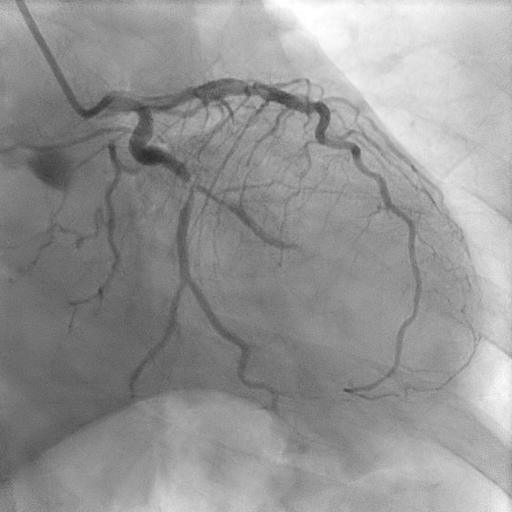

Coronary angiogram showed two vessel disease with severe stenosis at the obtuse marginal (OM), distal left circumflex (LCx) artery and distal right coronary artery (RCA) with mild disease at the proximal left anterior descending artery (LAD).